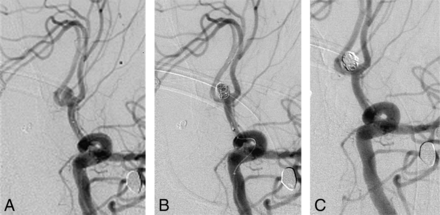

Another treatment option for wide-neck aneurysms is temporary stent-assisted coiling.12,13 For this purpose, 2 microcatheters are used. The first microcatheter is used to cover the aneurysm neck and deploy the stent. The second microcatheter is advanced into the aneurysm to perform coil embolization. Advancement of the second microcatheter into the aneurysm can be performed either before deployment of the stent or after stent deployment.14 The stent is deployed to cover the aneurysm neck but is not fully released. After coil embolization has been completed, the stent is recovered (Figs 1 and 2). In the unlikely event of coil protrusion during the process of recovery of the stent, recovery is stopped, the stent is deployed again, and it is released for permanent implantation. Temporary stent-assisted coiling is an established standard technique in our institution for the treatment of wide-neck aneurysms. Because to date, only case reports and small case series have been published, we analyzed a larger cohort of patients treated with temporary stent-assisted coiling.12,13 Following, we present a retrospective analysis on the effectiveness and safety of temporary stent-assisted coiling.

A, An aneurysm of the anterior communicating artery before coiling. B, The same aneurysm partially coiled with a deployed Solitaire stent from the left A1 to the right A2 segment. C, The same aneurysm after complete coil embolization. The Solitaire stent has been recovered.